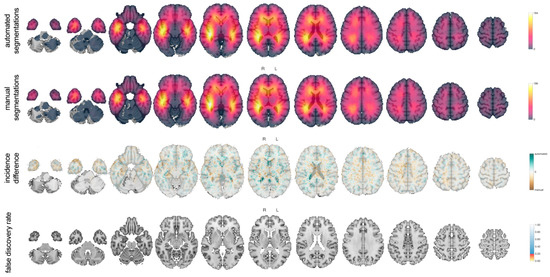

3.2.7. Tumor Probability Map

3.3. Examples of Disagreement between Manual and Automated Segmentations